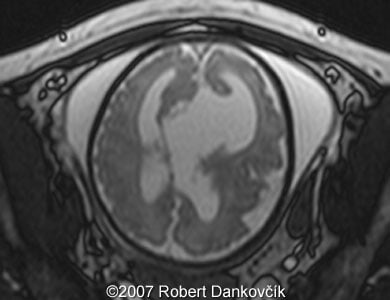

Images 8, 9: MRI; 32 week of pregnancy; transverse sections through the fetal skull showing dilated lateral ventricles and dominant interhemispheric cyst extending to the right.

9

10

Images 10, 11: MRI; 32 week of pregnancy; transverse (image 11, left) and parasagittal (image 12, right) sections through the fetal skull showing dilated lateral ventricles and interhemispheric cyst.

11

12